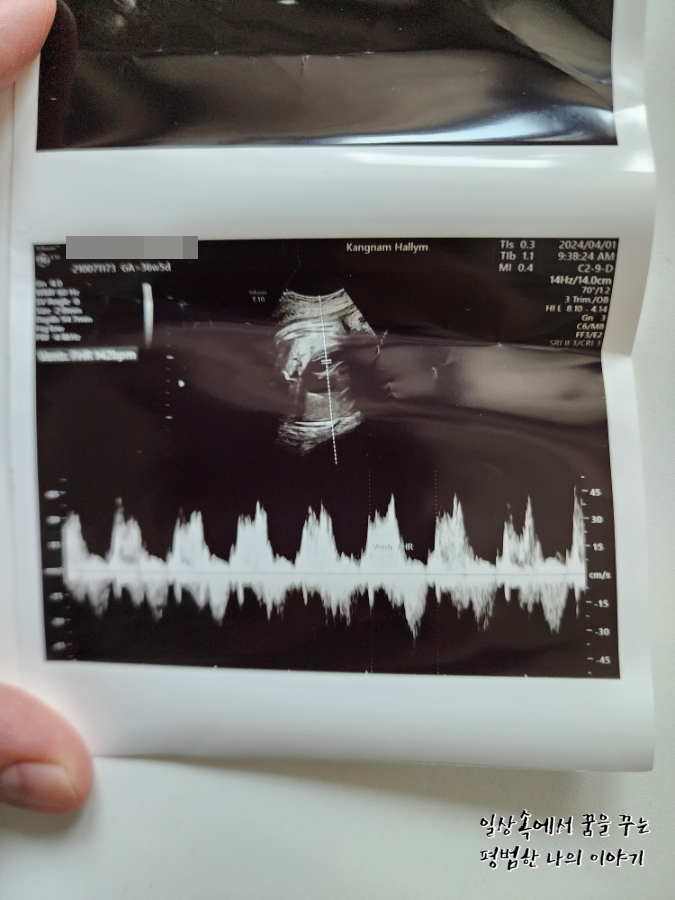

FHR(Fetal Heart Rate, 심장박동 수): 142bpm

원래 이번 주 목요일이 정기검진을 가는 날인데 이틀 전부터 계속 배가 생리통처럼 살살 아프고 아래쪽이 묵직하면서 뻐근한 게 심상치 않아 오늘 병원을 갔다. 지난번 방문보다 많이 커있지 않기를 바라며 방문했지만 아니나 다를까 지난번에 비해 거의 550g 정도가 늘어 이제 3.8kg에 육박하는 것이 아닌가. 첫째 39주 차 때와 비교하니 사이즈가 비슷하다.(머리둘레, 배 둘레, 허벅지뼈 등) 의사 선생님이 지난번 방문 때까지만 해도 최대한 39주 이후에 유도 분만 날짜를 잡는 게 어떠냐고 하셨었는데 이번 방문에서는 아무래도 4월 11일 혹은 12일, 늦어도 15일 전에는 유도 분만 날짜를 잡는 게 낫겠다고 하셨다. (그때면 38주를 살짝 넘긴 시점) 그러면서 제왕절개도 염두에 두고 있어야 할 것 같다고 하셨다. 머리 크기도 배 둘레만큼 차라리 커버리면 유도 분만할 때 괜찮은데 머리둘레가 배 둘레만큼이나 큰 편이 아니라서 나오다가 어깨나 배에 걸려서 탈골이 되거나 난산이 될 수도 있다고 하시더라. 그렇다고 자연분만을 포기하고 아예 제왕절개로 결정하기에는 첫째도 자연분만으로 잘 낳았고 회복도 빨랐기에 아쉬움이 남으니 우선 다음 주 월요일에 마지막으로 검진을 하고 결정하자고 하셨다. 첫째가 우량아여서 둘째도 우량아겠거니 했지만(막상 지금 20개월 첫째는 우량아가 아님, 그냥 평균적으로 크고 있음) 이렇게까지 클 줄이야 상상하지 못했다.

아직 경부 길이가 출산을 할 정도로 짧아지거나 자궁문이 열린 것은 아니지만 경산이므로 진통이 지금처럼 있다가 갑자기 진통이 세지면서 출산을 하는 경우도 종종 있기 때문에 이번 주에 혹시라도 진통이 세지거나 하면 언제든 분만실로 오라고 하셨다. 회음부도 너무 부어있고 아기도 무거워서 많이 힘들 거라고 격려를 해주셨는데 눈물 날 뻔... 아무래도 이 힘듦은 나만이 아는 것이기 때문에 주변에 아무리 얘기한다 한들 이해받기 어려워 얘기하지 않고 혼자 꾹 참고 있었는데 뭔가 의사 선생님의 말이 위로가 되었다. 다행히 이번 주부터는 남편도 아기가 언제 나올지 몰라 일주일에 4번을 재택근무하게 되어서 마음이 좀 놓인다.